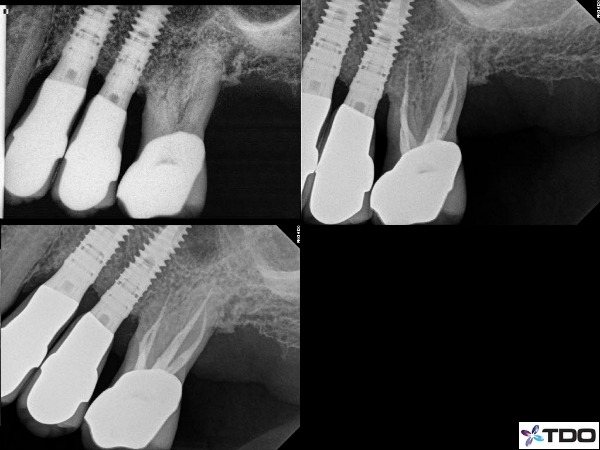

–lateral lesion caused by a lateral canal that harbors bacteria (figure 1)

Fig.1 Here is a case of a furcal lesion treated by Dr. Michael Sherman. In the radiograph in the upper right you can see a small lateral canal on the mesial root communicating with the furcation. That lateral canal is filled with sealer and the 2 year recall shows excellent healing.